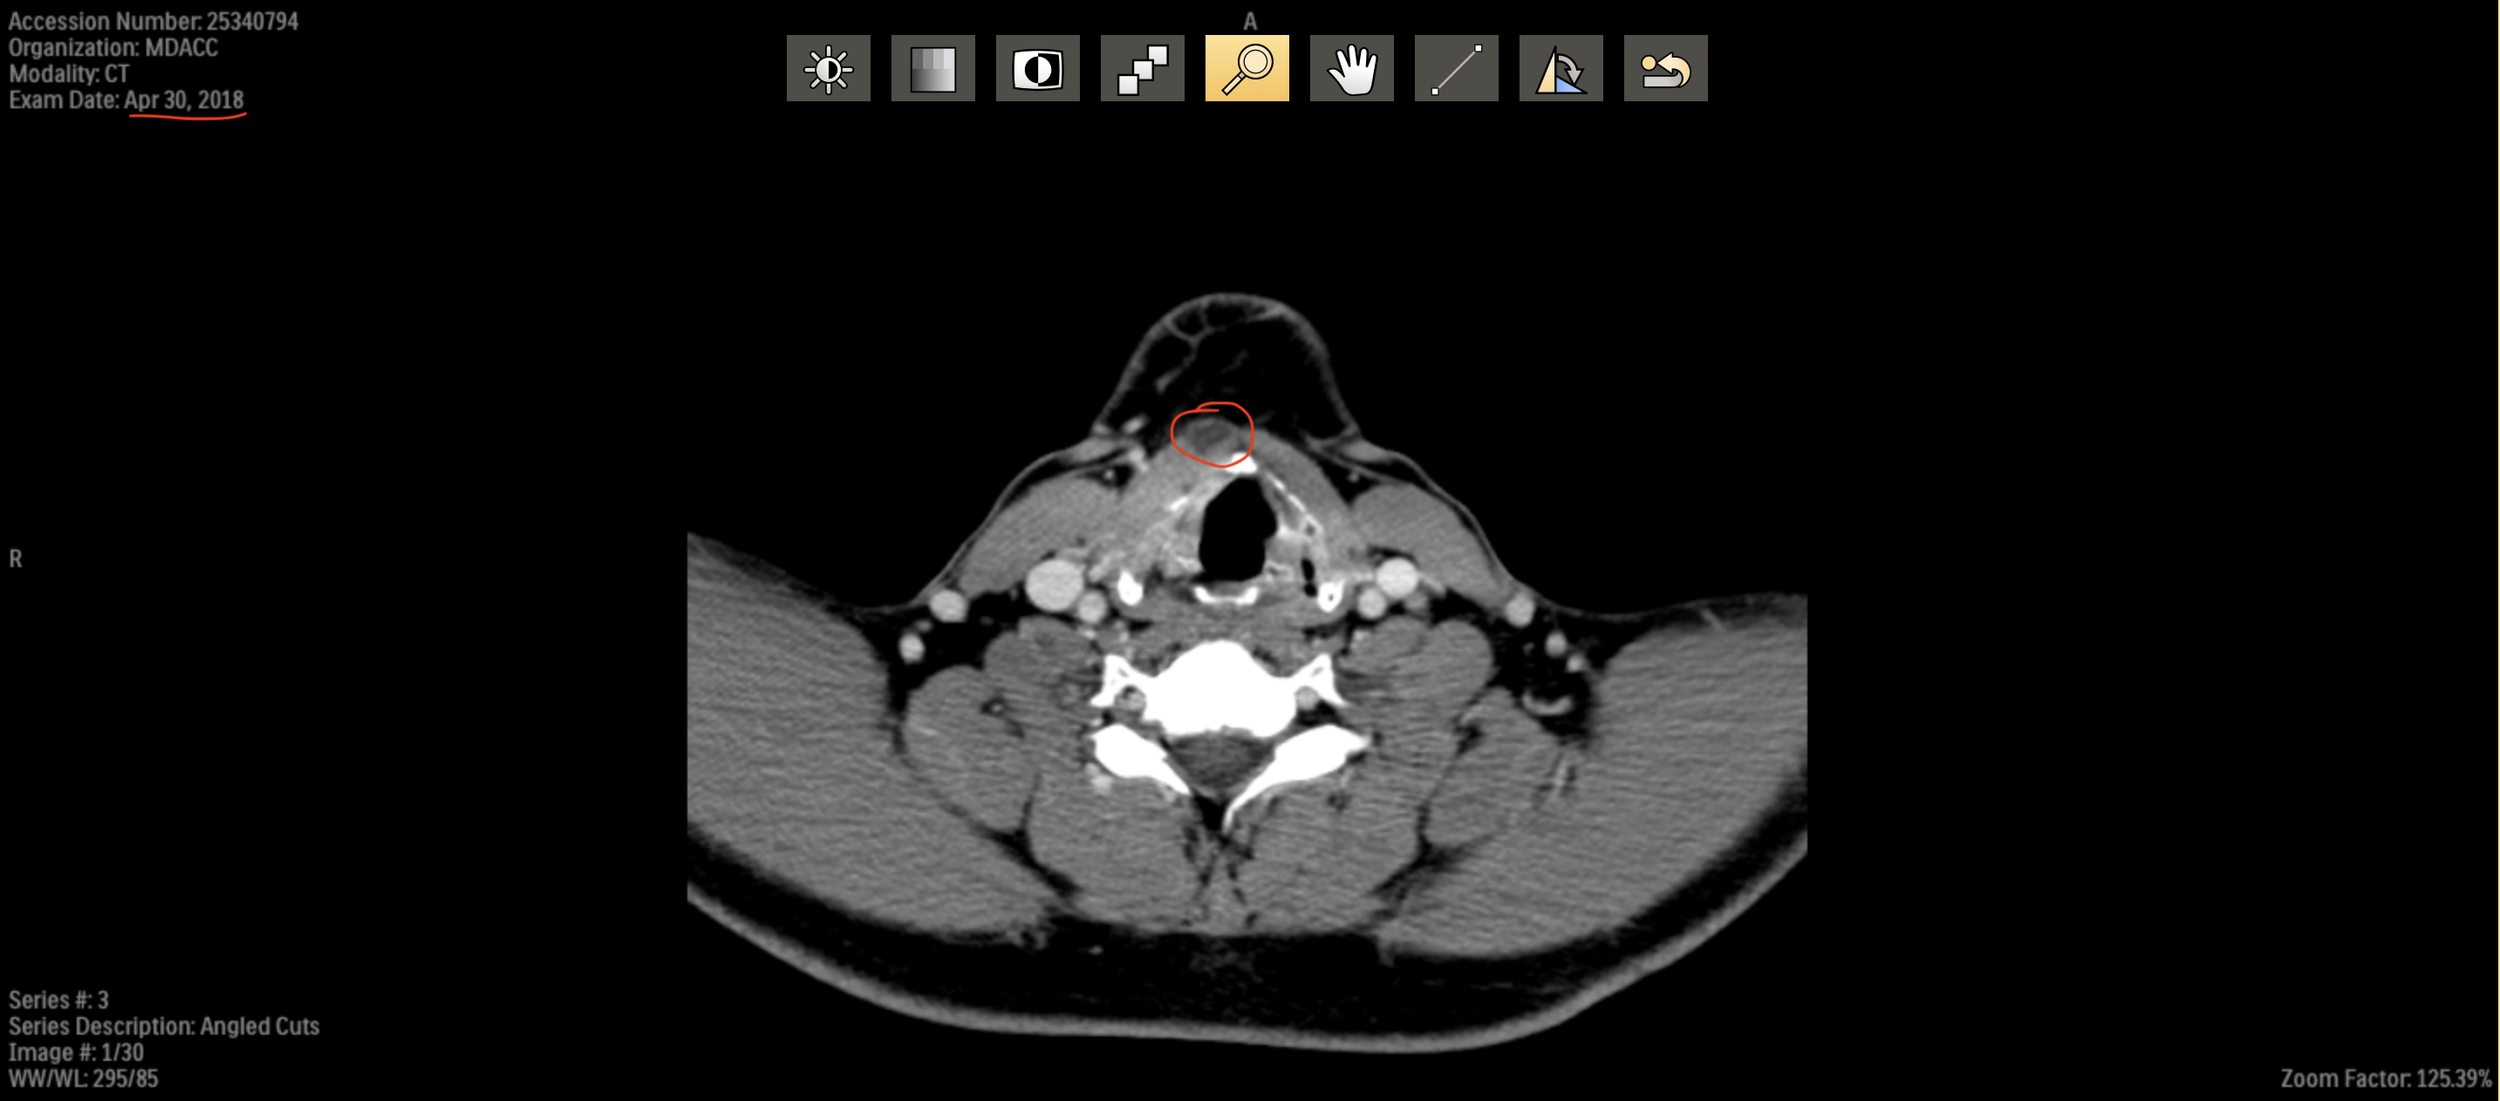

CT from 30 April 2018 (pre-treatment) shows the thyroglossal duct cyst (circled in red). Not infected at the time

The course of how to treat the remnant will be determined after getting an ultrasound, CT and biopsy. We did review some of my previous scans and he showed me how it appears. The duct was present in my 2018 pre-treatment scans, so that does confirm the congenital nature. The options are a) monitor and do nothing and b) surgically remove the duct and possibly the thyroid gland as well. We will re-assess on my September visit. The only issue is that if I do elect surgery, it’s best to do it sooner, before another infection flares up. So that could be an intermediate trip back to Houston between my regular follow ups in Sep and Dec/Jan.